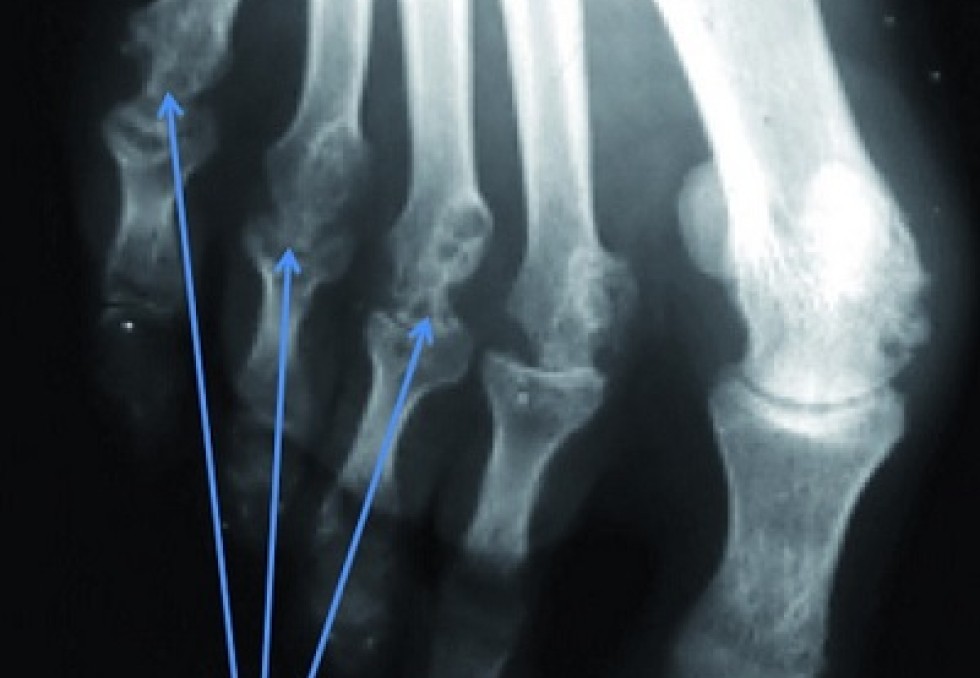

Le dernier né est Kevzara (sarilumab), le premier anticorps monoclonal anti-IL6R en administration sous-cutanée toutes les deux semaines. Sa première indication est la polyarthrite rhumatoïde (PR) active, modérée à sévère, seul ou en association au méthotrexate (MTX) en cas de réponse insuffisante ou d’intolérance au MTX. Pour annoncer ce lancement, Sanofi Genzyme, désormais unité opérationnelle mondiale de Sanofi pour les maladies rares, la SEP, l’immunologie et l’oncologie, avait convié Gérard Thibaud, Président de l’Association nationale de défense contre l’arthrite rhumatoïde (Andar). Entendre la voix du patient dans une telle pathologie est essentiel afin de comprendre l’importance de l’innovation thérapeutique. Victime de cette maladie depuis plus de 40 ans, ce patient a bénéficié en 2010 de sa première biothérapie : "un véritable miracle", dit-il, après tant d’années marquées par les déformations articulaires que ni la chirurgie palliative ni le MTX ou les corticoïdes n’avaient pu éviter. Pour la première fois depuis des décennies, grâce à un premier antiTNF-alpha, Gérard Thibaud pouvait enfin faire de longues marches, porter ses petits-enfants, lui qui n’avait jamais pu porter son enfant. Jusqu’à la première rechute par un phénomène d’échappement thérapeutique, un événement encore plus difficile à vivre, selon lui, que l’annonce de la maladie. C’est à ce moment-là qu’on comprend toute l’importance d’un traitement biologique supplémentaire qui permettra de sortir de l’impasse thérapeutique. Aujourd’hui, Gérard Thibaud en est à sa 3e biothérapie avec une qualité de vie satisfaisante. Bloquer la capacité destructrice de l’interleukine 6 Les Prs Alain Cantagrel (CHU de Toulouse) et René-Marc Flipo (CHU de Lille), respectivement président et secrétaire général de la Société française de rhumatologie, se sont relayés pour présenter ce nouveau biomédicament qui doit permettre d’atteindre l’objectif thérapeutique de tout cas de PR : l’obtention et le maintien de la rémission marquée par l’absence de signes et de symptômes d’activité inflammatoire. Sept essais multicentriques, notamment l’étude Mobility, incluant un total de 2 887 patients, ont assuré le plan de développement de Kevzara dont bénéficient déjà plus de 5 000 patients dans 15 pays. Le sarilumab est un anticorps monoclonal humain qui se lie de manière spécifique aux récepteurs solubles et membranaires de l’interleukine 6 (IL-6), une cytokine retrouvée à un taux élevé dans les articulations des patients atteints de PR et jouant un rôle important dans la destruction articulaire. Kevzara s’administre en sous-cutané toutes les deux semaines. Le stylo prérempli peut être conservé à température ambiante durant 15 jours, donnant une autonomie d’un mois à un patient ayant retrouvé sa mobilité.